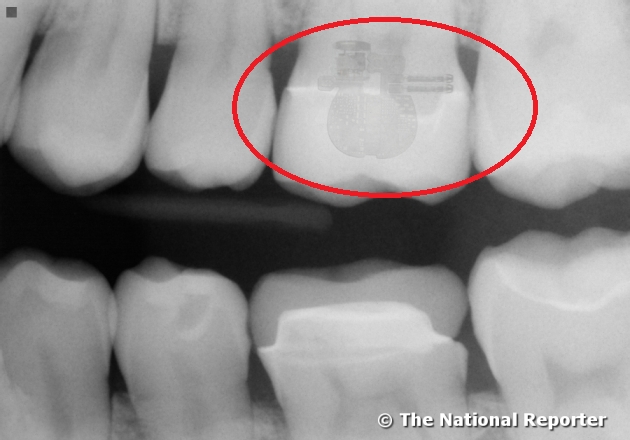

Vật thể kim loại bí ẩn được phát hiện trong răng ông Hánon. (Ảnh: soundofhope.org)

Khi Wally Hanson ghé thăm nha sĩ để kiểm tra, một vật thể kim loại bí ẩn được phát hiện trong răng ông. Theo Hanson, ông không thể hiểu nổi làm sao cái vật bí ẩn này lại được cấy trong răng của mình và nha sĩ của ông, bác sĩ Fred Wallington nói rằng bản chụp X quang của Hanson cách đây một năm hoàn toàn không có nó.

Hình ảnh phóng to của thiết bị kỳ lạ trong răng của ông Hanson. (Ảnh: soundofhope.org)